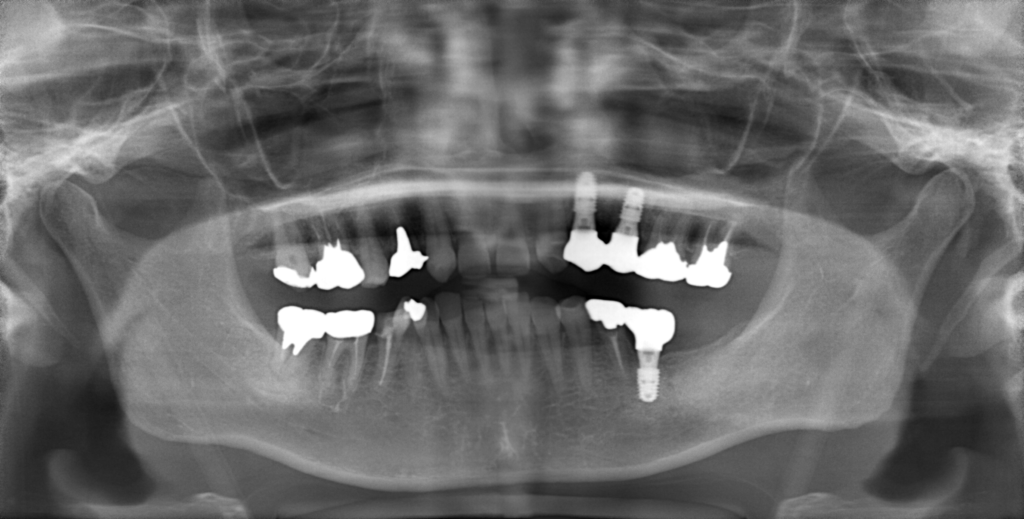

Y様インプラント実例 #44

左の上下の奥歯をインプラントで治療しています。

左下の奥歯は歯を抜くのと同時にインプラントの埋め込みを行っています。

被せものは上下、セラミックスで作っています。

治療前

治療後